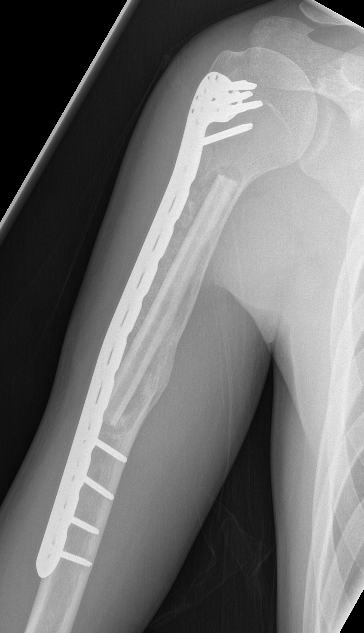

ORIF and bone graft

Indication

- fracture

- weight bearing bone

ORIF + fibular strut allograft

Jamshidi et al Int Orthop 2018

- 14 cases humerus UBC

- treated with locking plate + fibular allograft

- complete healing in 10, partial healing in 4